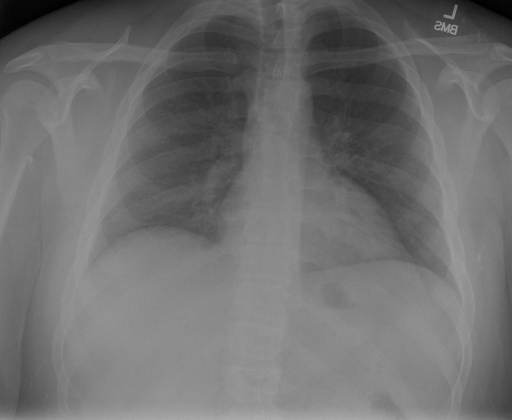

|X光影像|诊疗报告(医生)|XrayGLM|

||根据X射线图像,心脏大小正常,肺部看起来很清晰。已经排除了肺炎、积液、水肿、气胸、腺病、结节或肿块的存在。该发现表明一切正常。换句话说,总体印象是胸部正常。|X光片显示,心脏大小正常。肺部没有气胸或胸腔积液的证据。骨骼结构看起来没有任何异常。总的来说,X光片表明没有发现急性心肺疾病的迹象。|

||X光图片显示没有扭曲的区域、可疑的骨质不透明度或胸腺积液。心脏大小轻微增大,但非常稳定。此外,没有气胸的证据,肺野也正常。总体来说,X光片显示没有急性心脏异常,但要注意轻微的心脏扩大。|X光片显示,心脏大小正常。肺部和纵隔轮廓清晰,没有气胸或胸腔积液的证据。骨骼结构完整,没有任何急性异常。|

||心影形态在正常范围内。没有急性骨质异常。有可能出现没有明显的吸水或肺实质状况的线索。没有大面积积液或气胸。有可能怀疑其有误吸或肺实质问题。为了确诊和治疗,可能需要进行适当的影像学随访。|心脏大小正常,肺部和纵隔轮廓清晰。没有急性异常或活动受限的证据。没有任何明显的气胸、胸腔积液或肺不张的迹象。此外,也没有发现任何局灶性骨质异常或其他急性疾病。|